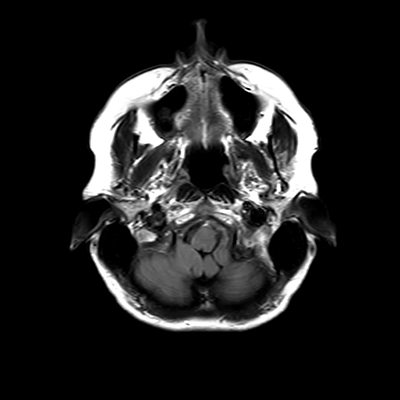

You also obtain an MRI of his brain once it's clinically safe to do so.

MRI brain (FLAIR)